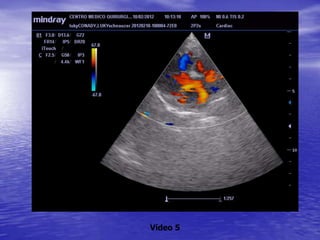

ECOCARDIOGRAFIA

Aorta

Ventrículo

derecho

Aurícula

izquierda

Pericardio

izquierdo

derecha

Válvula

tricúspide Válvula

mitral

Vídeo 5